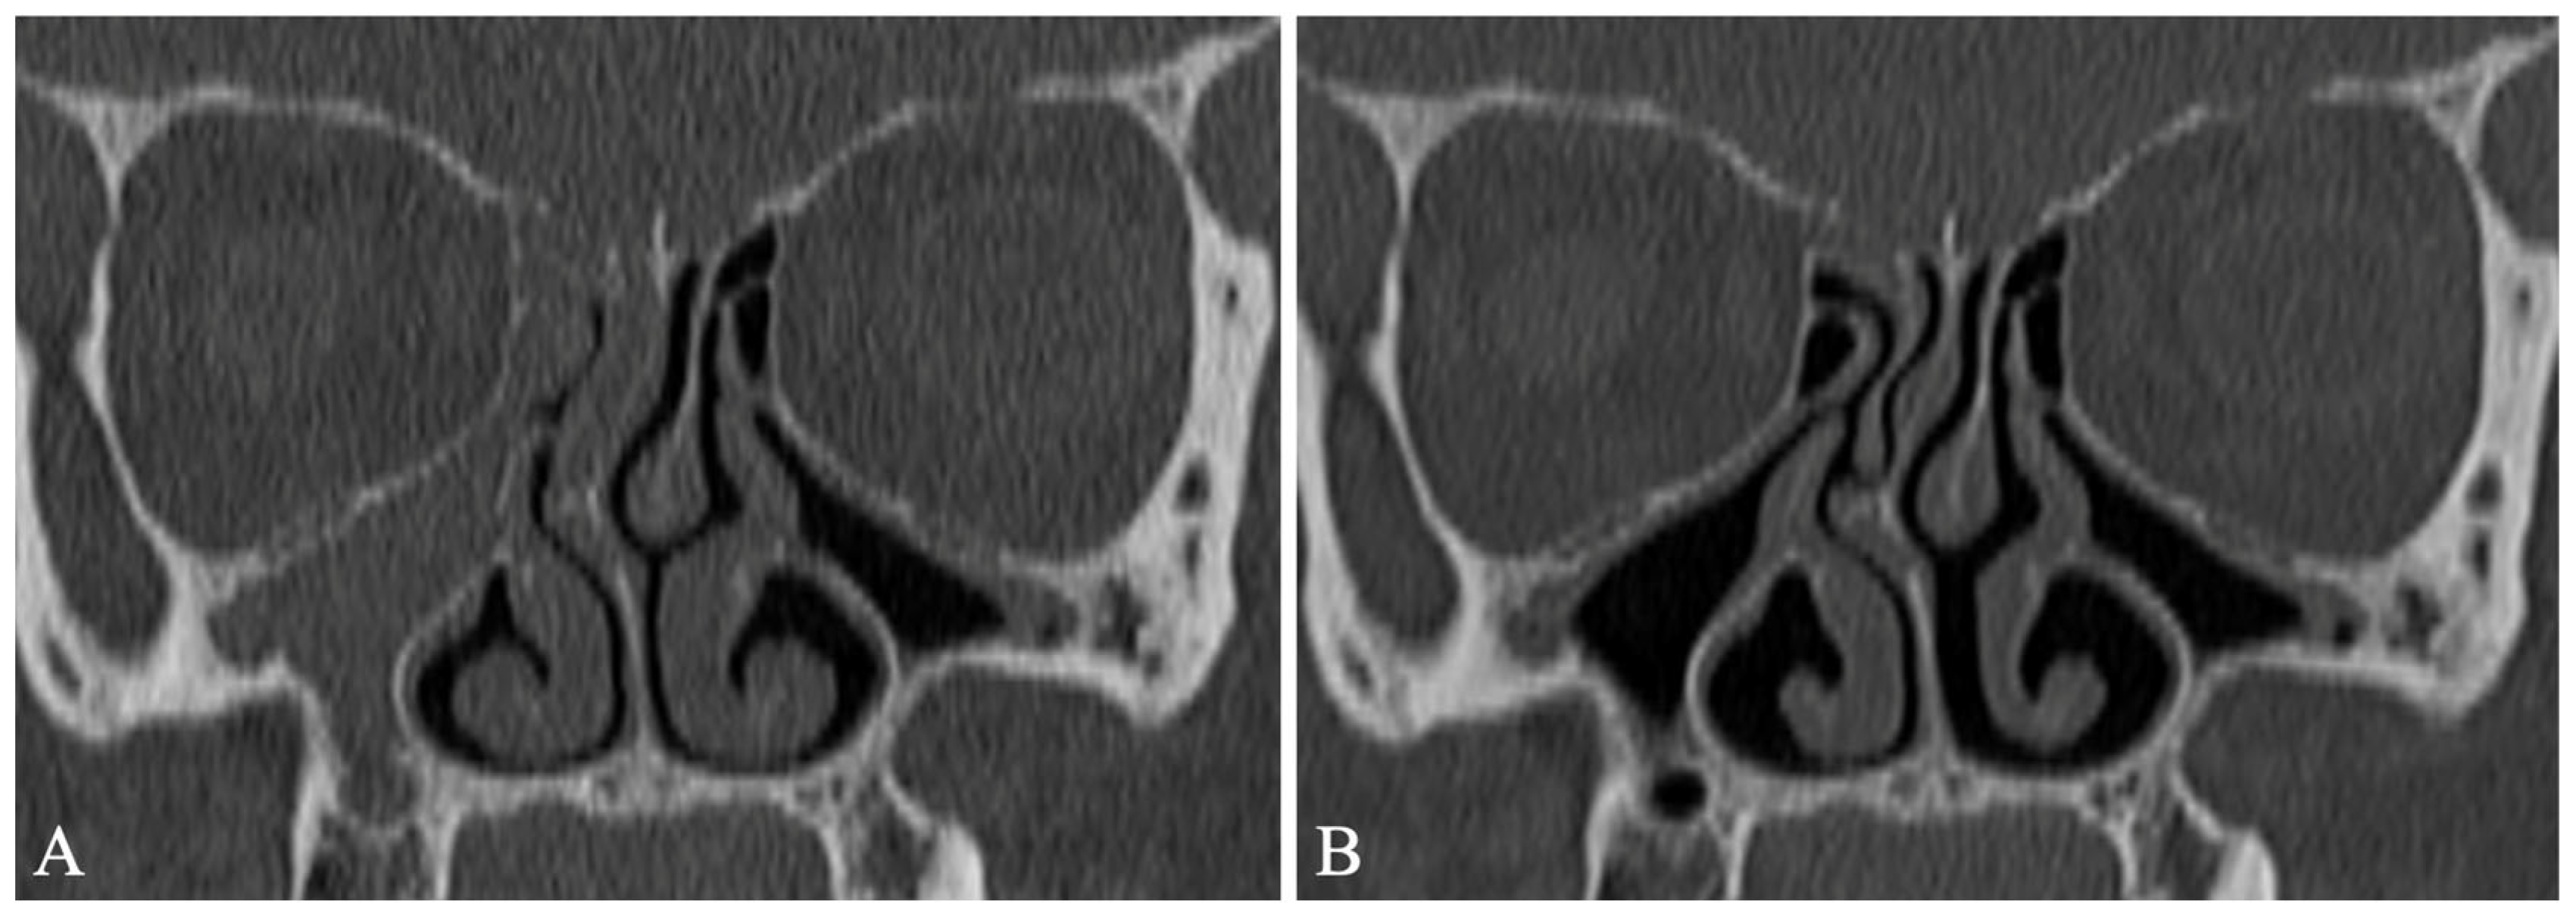

More recent studies have shown that ETI is efficacious in treating CF-CRS. Specifically, ETI has been shown to significantly improve patient-reported sinonasal outcomes, reduce sinus opacification on computed tomography (CT) scans, and reduce nasal polyp burden on nasal endoscopy (Figure 2) [71,72,73]. In contrast to these improvements CRS severity, treatment with ETI did not lead to improvement in olfactory dysfunction among PwCF—specifically, CT opacification of the olfactory cleft and Smell Identification Test (SIT) scores did not improve [27]. It is possible that earlier intervention with HEMT may improve or prevent olfactory dysfunction; additional studies are needed to investigate this theory.

Figure 2.

Coronal sinus computed tomography images of a person with cystic fibrosis before (A) and after six months (B) of elexacaftor/tezacaftor/ivacaftor treatment. This twice daily oral therapy leads to an improvement (decrease) in sinus opacification.